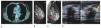

Es el método de elección en la paciente con mamaplastía de aumento y probabilidad de cáncer mamario, así como en la valoración de la integridad de los implantes, sobre todo cuando se sospecha ruptura intracapsular, la cual no se observa en la mastografía y la sensibilidad en el ultrasonido es baja para esta complicación, en este caso puede efectuarse la RM sin contraste, o en la sospecha de otras complicaciones de las prótesis (figs. 10A-D).

Figura 10 A) Paciente asintomática de 41 años, prótesis mamaria derecha de silicón, subpectoral con deformidad del contorno superior (flecha). B) Agujero negro derecho con "signo de la escalera", descartar ruptura intracapsular, BIRADS 0, se recomienda resonancia simple. C) y D) Secuencia para silicón con "signo de Linguini" derecho, ruptura intracapsular (flechas); prótesis izquierda sin alteraciones: BIRADS 2.